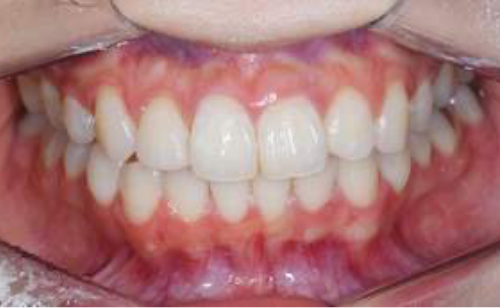

現在のお口の状態を写真で記録し治療後と比較したり、治療説明で利用します。

お口の中の変化を見逃さないために検診時にお口の中のお写真を撮らせていただきます。

治療後も定期検診を継続していくことで綺麗な口腔内が維持できます。